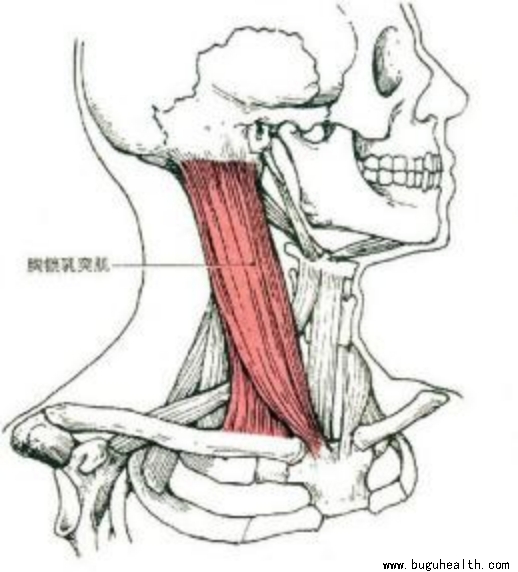

关于上交叉,日常的驼背探颈等习惯使得斜方肌上束、斜角肌、胸锁乳突肌紧张,使得颈部压力变大,出现疼痛。